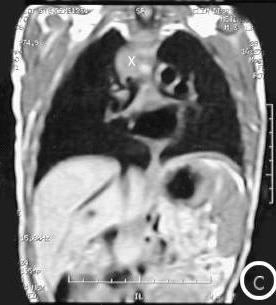

Resonancia Magnética

Corte longitudinal antero-posterior:

• Foto A: Corte longitudinal antero-posterior a la izquierda de la traquea. (X) = Masa mediastinal antero-superior en su extensión lateral izquierda de la traquea.

• Foto B: Corte longitudinal antero-posterior a la derecha de la traquea: (X) Masa mediastinal antero-superior en su extensión lateral derecha traqueal.

Corte trasversal detrás de la traquea.

• Foto C: (X) = el extremo derecho de la masa mediastinal.